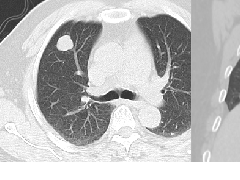

肺内淋巴结的CT表现特点及与病理对照  肺实变与肺不张的CT鉴别诊断

肺实变与肺不张的CT鉴别诊断  医生现身说法,这五种忙帮不得!